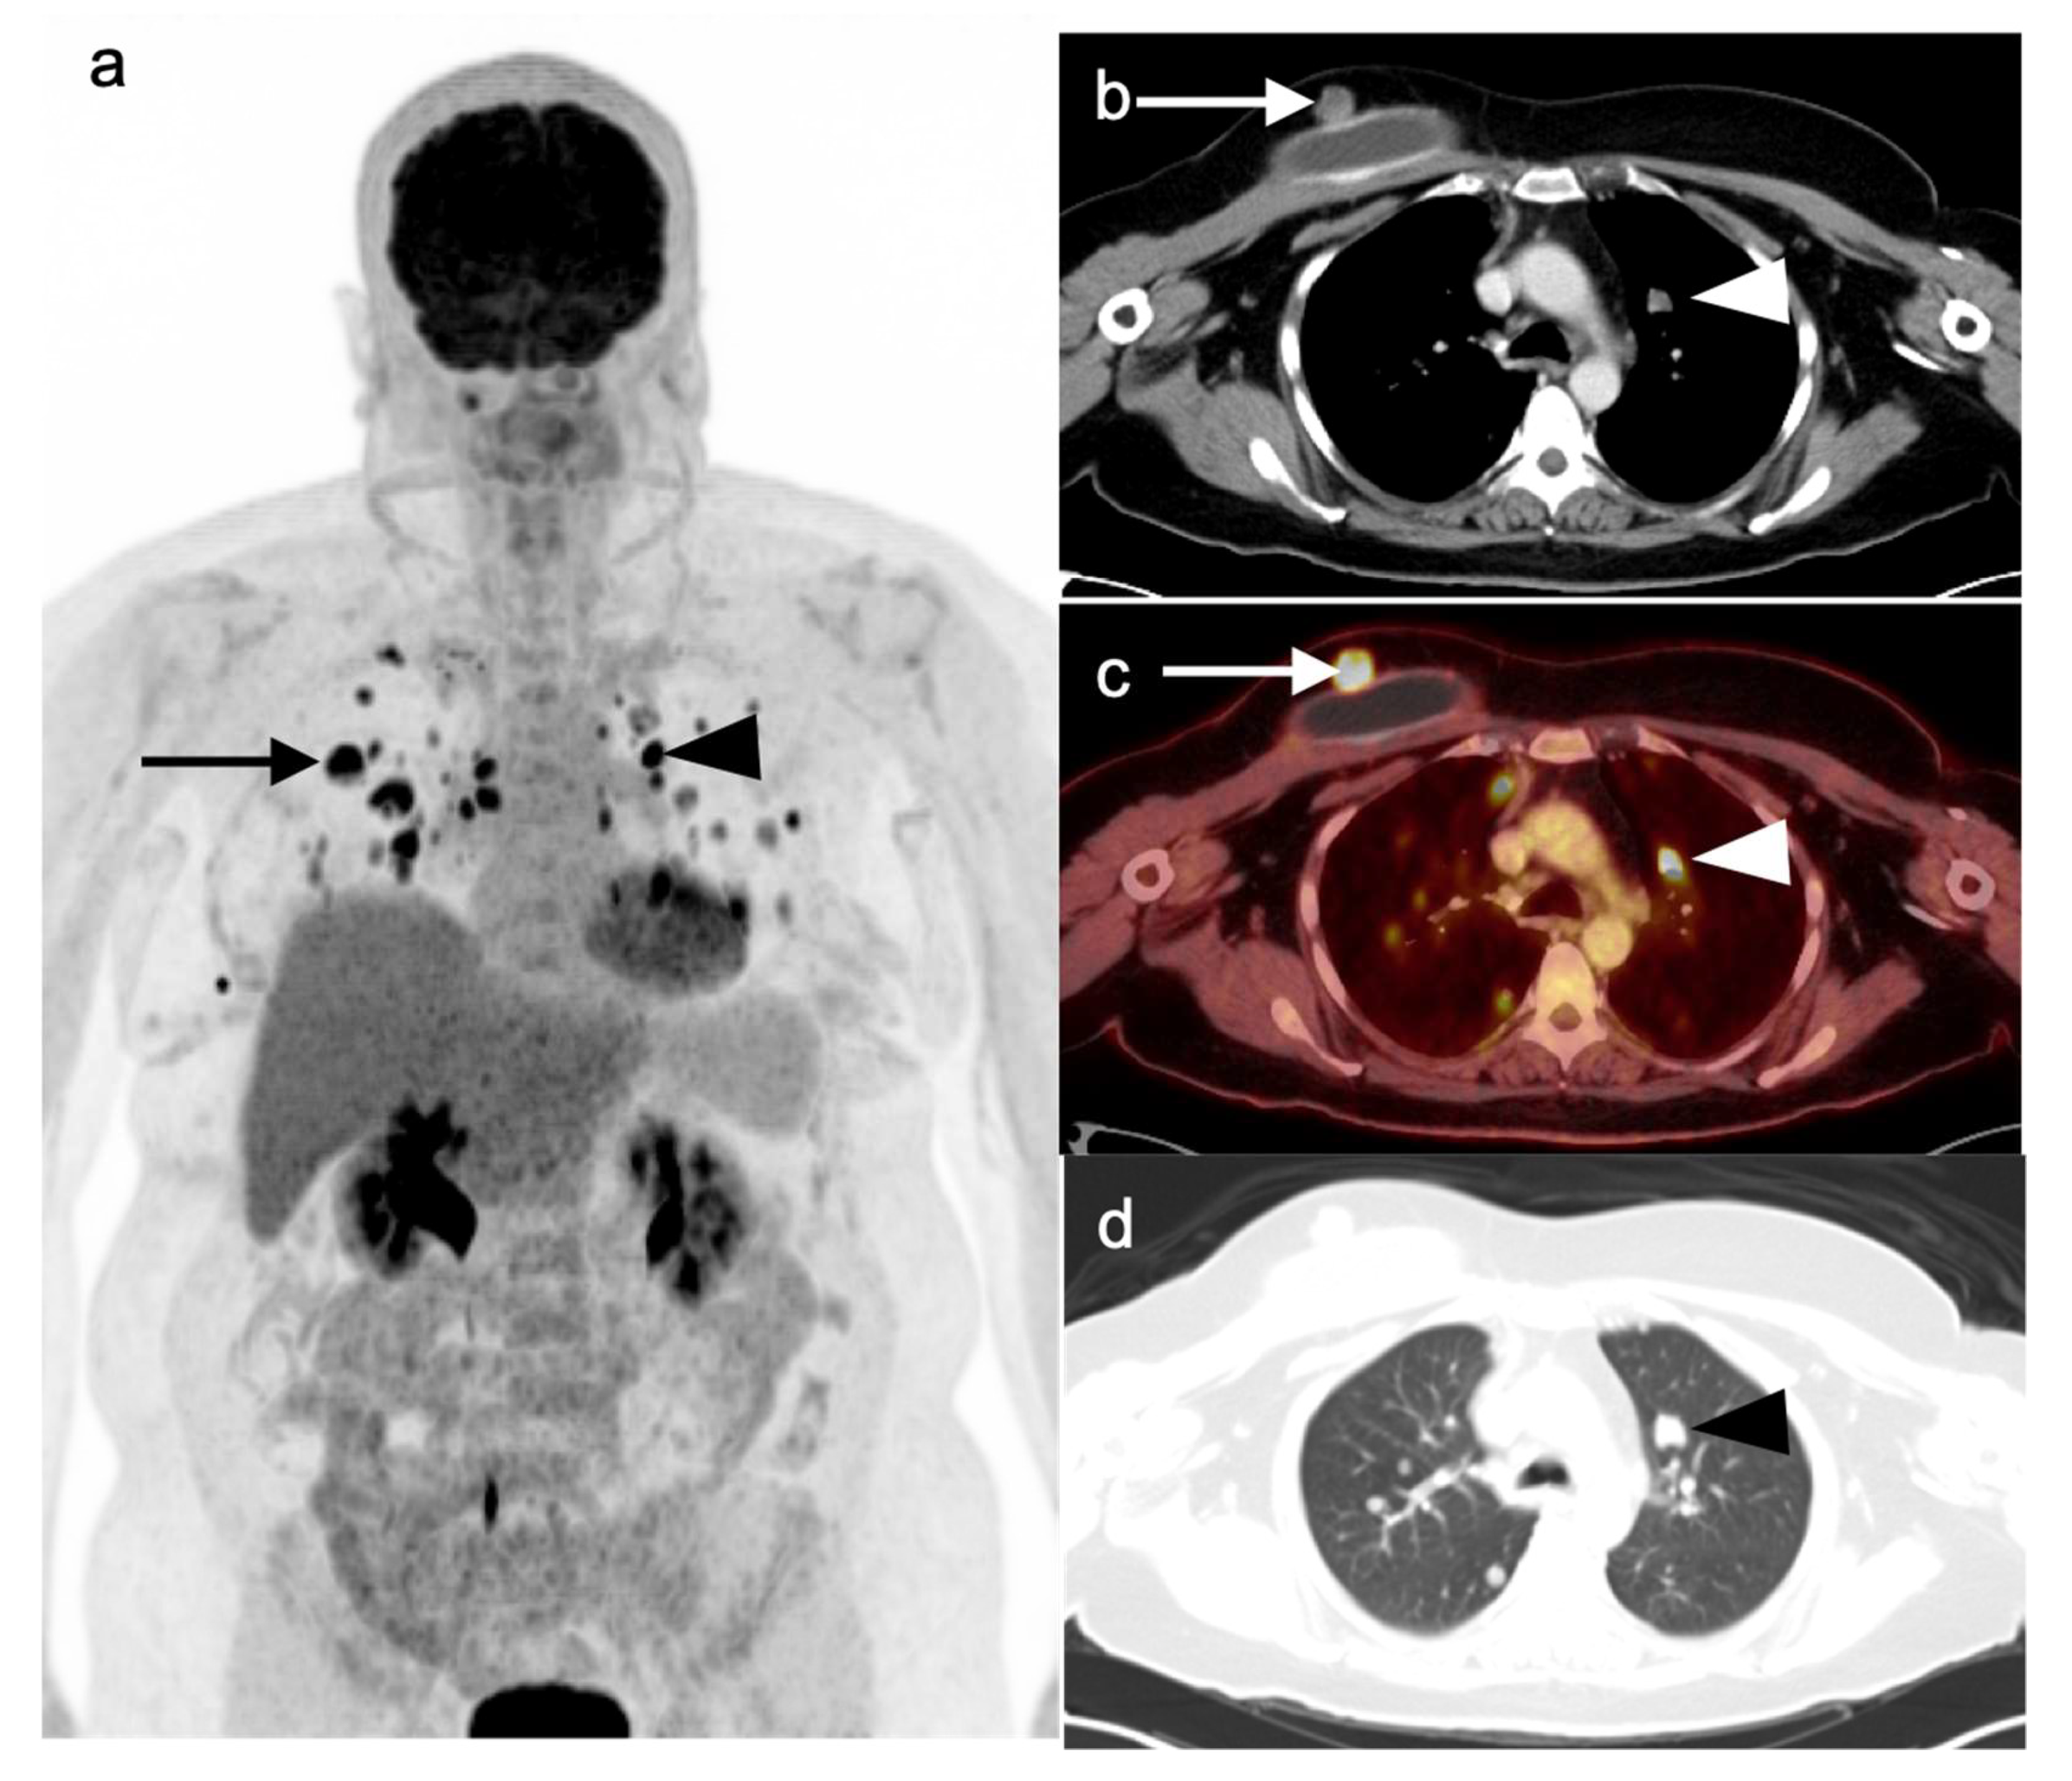

Nearly half of all patients with NSCLC have distant metastatic disease at initial diagnosis and identification of distant metastases is of major importance in the management and prognosis. Additionally, among patients who have been treated with radical and supposedly curative therapy, approximately 20% are likely to develop recurrent disease due to undetected foci of metastasis at initial M staging. Distant metastases are most commonly seen involving the brain, skeleton, liver, and adrenal glands in descending order of frequency (Figure 10) [31]. Traditional evaluation for distant metastatic disease includes CT scans of chest, abdomen, and pelvis, brain imaging with CT or MRI and bone scintigraphy [2]. However, FDG PET-CT has been shown to be great utility in M staging of the patients with NSCLC, specifically if the patients present with clinical manifestations of metastatic disease. Additionally, FDG PET-CT has been shown to provide more pertinent information during the preoperative assessment than is CT alone, except in the assessment of brain metastases, in a situation where the two modalities yield similar results [32]. For staging mediastinal lymph nodes, diffusion-weighted imaging MRI (DWI) and FDG PET-CT showed similar performance in staging of mediastinal lymph nodes, supporting the idea that DWI may offer an alternative to FDG PET-CT in some cases [33].

2.4. Small Cell Lung Cancer

Small cell lung cancer (SCLC) is an extremely aggressive tumor type which accounts for about 10–15% of all lung cancer cases [38,39]. It originates from neuroendocrine precursor cells and is characterized by rapid growth and early metastatic potential, with approximately 70% of patients presenting initially with metastases [40]. Up to 10–25% of patients with SCLC have brain metastases at the time of initial diagnosis and an additional 40–50% will develop brain metastases during the course of their disease. Although SCLC is usually chemo-sensitive in the early stages and sensitive to radiation therapy, most patients with SCLC will experience recurrent disease leading to death. Over 95% of patients with SCLC are either current or former smokers [2]. According to the Veterans Administration Lung Group’s criteria, SCLC has been traditionally divided into two stages—a binary system of staging—limited disease and extensive disease [41]. Limited-stage disease SCLC (LD-SCLC) is disease confined to ipsilateral hemithorax, mediastinum (including contralateral mediastinal nodes), and ipsilateral supraclavicular nodal involvement, which can be encompassed within a single radiation field (Figure 11) [42]. Extensive-stage disease SCLC (ED-SCLC) is spread beyond the ipsilateral hemithorax including hematogenous metastatic disease and presence of malignant pleural or pericardial effusion (Figure 12) [39,43]. Standard therapy for patients with LD-SCLC includes chemotherapy in conjunction with radiation therapy. Due to high potential for developing brain metastases in this group of patients, palliative cranial radiation is also indicated to increase overall survival. In ED-SCLC, only systemic chemotherapy is considered, as a palliative treatment, because long-term survival in these patients is rare [43,44]. According to the more recently adopted AJCC (American Joint Commission on Cancer) TNM staging system 8th edition, there is no significant difference between NSCLC and SCLC in the staging system [26]. The NCCN Panel adopted a combined approach for staging SCLC using both the AJCC TNM staging system and the VA scheme for SCLC. In applying the TNM classification to the VA system, the so-called limited-stage SCLC is defined as stage I–III (any T, any N, and M0, respectively), which can be effectively treated with definitive radiation therapy and extensive-stage SCLC is defined as stage IV (any T, any N and M1a/b) or T3–T4, harboring multiple lung nodules or tumor volume that is too large to be encompassed in a tolerable radiation plan/field.